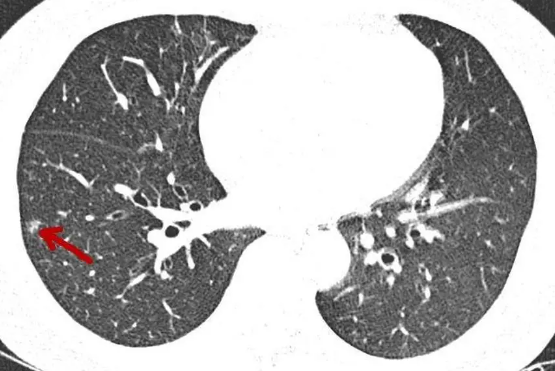

4、如何判断结节的良恶性?

这是非常专业的知识,请交给专科医生来判断。但从临床经验来看,以下几点比较有普遍性:(1)小而实的结节多数是良性;(2)持续存在的纯磨玻璃结节基本是恶性,不过恶性度低,进展缓慢;(3)磨玻璃结节中瘤肺边界清楚的多为恶性;(4)实性结节边界光整比较圆形的良性可能更大,而若边缘有细毛刺、分叶、胸膜凹陷、空泡或空腔征等则容易是恶性;(5)实性成分若收缩纠集感比较明显,则恶性可能更大;(6)多发磨玻璃结节容易是多原发癌;多发实性结节则容易是良性病变。